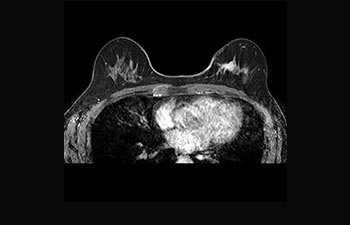

Mayor fiabilidad diagnóstica en neurooncología

Encuentre la aplicación clínica adecuada a sus necesidades